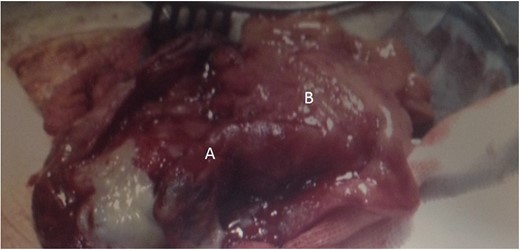

Through a left groin incision, the inguinal canal was opened and a thickened cord with signs of chronic inflammation was seen and mobilized. The sac was dissected free and opened, and its content inspected, revealing the presence of the caecum and of an inflamed appendix with a gangrenous tip (Fig. 1). An appendicectomy was performed and the sac was closed and reduced into the abdominal cavity in the standard fashion. At this stage, it was considered prudent to proceed with a hernioplasty without mesh. To facilitate a more robust sutured repair, we proceeded with a left-sided orchidectomy and a suture two-layer repair.

Left-sided inguinal hernia containing the VA (A) and caecum (B). Note the inflammatory changes and the gangrenous tip consistent with appendicitis.